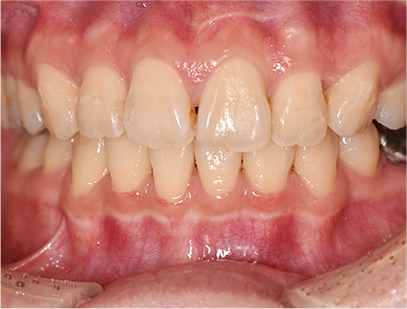

治療後

• 正面

治療前の写真と比べると上下の前歯は後方に下がりました。

そのために、鼻の下の膨らみもすっきりして、下唇も薄くなることができました。

治療期間は2年と6か月を必要としました。